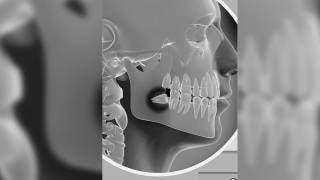

Ofrece Jiutepec campaña de extracción de muelas del juicio

Jiutepec, MORELOS.- Del 18 de mayo al martes 15 de junio el Sistema para el Desarrollo Integral de la Familia (DIF) Jiutepec ofrece a habitantes del municipio, en situación vulnerable, cirugías de terceros molares a bajo costo. El procedimiento es conocido coloquialmente como extracción de las “muelas del juicio”.